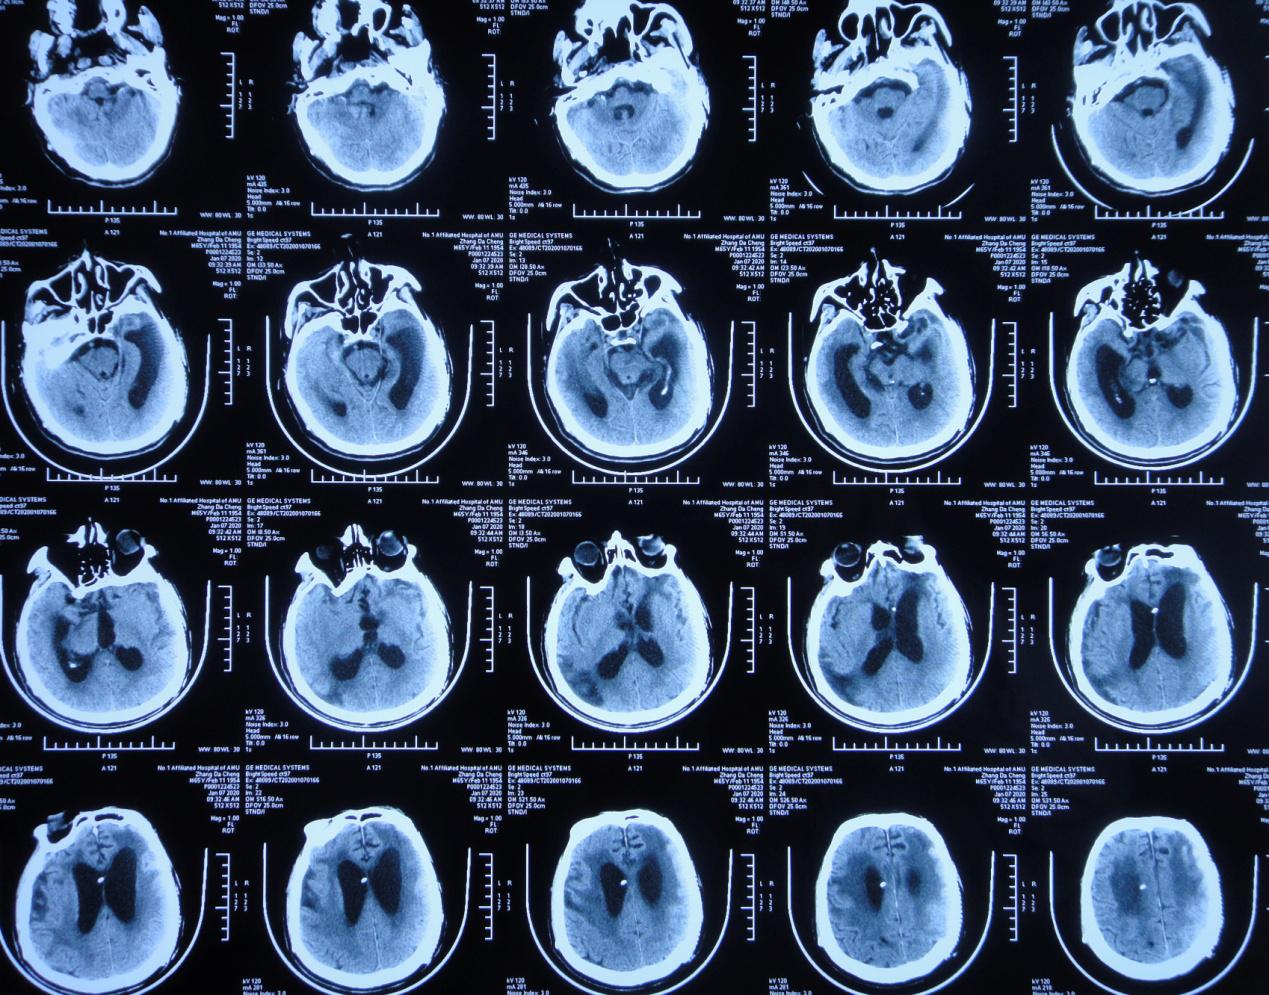

左颞叶血肿清除+去骨瓣减压术后第63天,即2019年9月11日患者言语较前清晰,单侧搀扶下可行走,复查头颅CT( 图-5 )(双颞增大)脑室较前仍无明显变化,但脑室周围水肿稍加重。

图-5: 2019年9月11日头颅CT

左颞叶血肿清除+去骨瓣减压术后第99天,即2019年10月17日患者言语基本清晰,可独立缓慢行走,复查头颅CT( 图-6 )示:颅脑术后改变,脑室较前无变化,脑室周围水肿较前无变化。

图-6: 2019年10月17日头颅CT